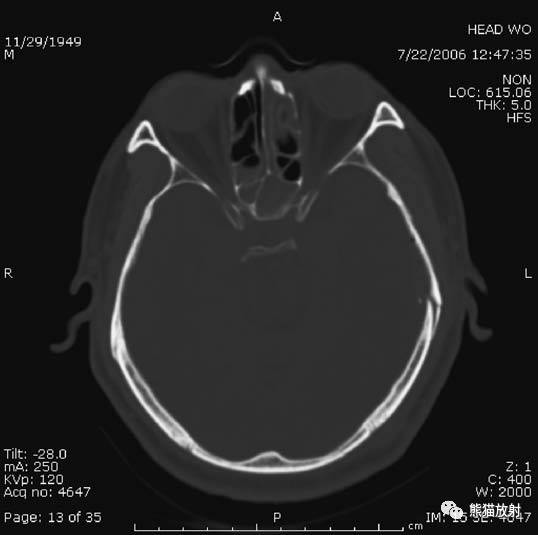

1、颅骨骨折

额骨骨折:左侧额窦内外侧壁骨折;

左侧颞骨骨折。